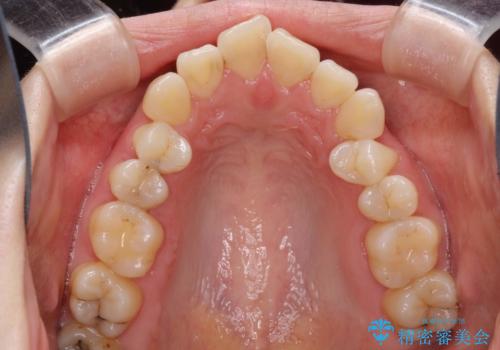

- 上顎両側第1小臼歯、下顎左側第2小臼歯の3本を抜歯、ラビアルのワイヤー矯正を計画した。

抜歯矯正は抜歯にできたスペースをつかい、前歯を積極的に下げたり、大きなガタつきを取り除くことができますが、その分時間がかかります。